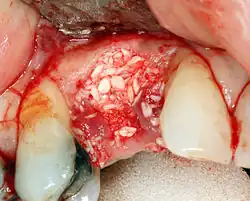

Guided Bone Regeneration

Neben dem Einbringen von Knochen oder Knochenersatzmaterial wird ein Verfahren der Guided Bone Regeneration (GBR) ‚Gesteuerte Knochenneubildung‘ angewandt.[5] Beim Verfahren der GBR wird der Raum, der mit Knochen aufgefüllt werden soll, zusätzlich mit einer Membran umgeben. Diese hat die Aufgabe, ein zu schnelles Wachstum der umliegenden Zellen des umliegenden Weichgewebes in den Hohlraum zu verhindern, da sich dieses schneller bildet als Knochen. Es können resorbierbare und nicht-resorbierbare Membranen verwendet werden. Überwiegend werden resorbierbare Membranen verwendet, da damit ein zweiter Eingriff zum Entfernen der Membran vermieden wird und seltener Wundheilungsstörungen auftreten, insbesondere bei einer Dehiszenz des Mukoperiostlappens, der als Wundverschluss dient. Nichtresorbierbare Membranen bestehen aus titanverstärktem Polytetrafluorethylen (PTFE). Resorbierbare Membranen bestehen aus behandelndem Kollagen.[6]